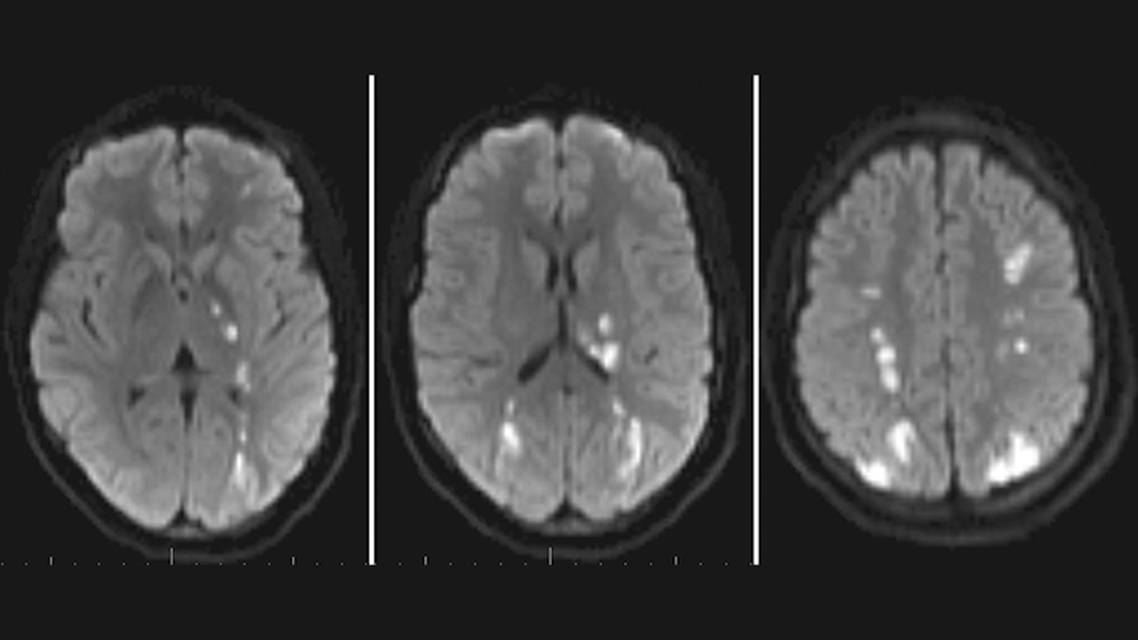

MRI performed at the outside hospital before transfer demonstrated bilateral middle cerebral artery (MCA)/anterior cerebral artery (ACA) and MCA/posterior cerebral artery watershed infarcts, with greater involvement on the left side, corresponding to the clinical presentation (Figure 1). No stenosis, occlusion, or other remarkable findings were visualized on initial CT angiography. Acute vision loss and worsening cognition on the second day of hospitalization prompted repeat MRI, which showed extension of parieto-occipital infarcts, and angiogram was performed. Cerebral angiogram revealed bilateral supraclinoid internal carotid artery (ICA) stenosis (right, 79%; left, 61%), without distal medium or small-vessel irregularity or beading to suggest a diffuse vasculitic process (Figure 2).